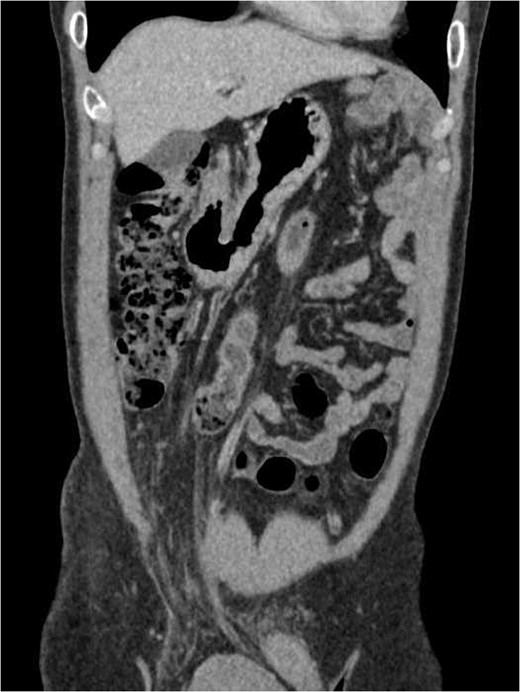

We proceeded with an ultra-sonographic examination of the scrotum, which revealed a heterogeneous mass within the right scrotal sac measuring 7.0 cm × 6.2 cm. The normal right testicle was not seen (Fig. 1). The features were pointing towards a right testicular tumour. Thus, a computed tomographic (CT) scan was ordered, which revealed a right inguinal hernia containing greater omentum and a heterogeneous mass suggestive of a right testicular tumour as seen on the ultrasonography (Figs 2 and 3).

Coronal view of the thorax and abdomen CT scan showing a right inguinal hernia containing greater omentum.